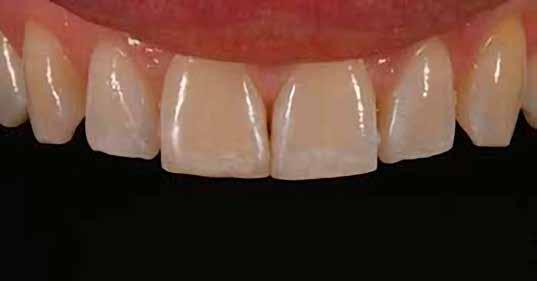

Egy 30 éves, negatív kórtörténettel rendelkező beteg azzal a kéréssel fordult hozzánk, hogy cseréljük ki az UR1 traumája után, 10 évvel korábban készült korábbi kompozit-helyreállítást.

A klinikai vizsgálat során az UR1 reagál a viabilitási tesztre, és az ugyanazon a napon készült röntgenfelvételen nem mutat periapikális elváltozásokat (1. ábra).

Az UR1 elszíneződött, és palatálisabb helyzetben van, mint az ellenoldali központi UL1 (2. ábra)

Az esztétikai elemzés a gingivális zenit aszimmetriáját mutatja az UR1 és az UL1 között. Parodontális szonda segítségével, plexusérzéstelenítés után, az IA

típusú funkcionális hám megváltozott passzív erupcióját igazoljuk Coslet és mtsai. osztályozása szerint (3. ábra)

A lehető legkonzervatívabb helyreállító kezelés elvégzése érdekében a páciensnél, figyelembe véve a megtartott fogelem korát és vitalitását, a tervezés és a diagnosztikai felviaszolás után a közvetlen kompozit-helyreállítás elvégzése mellett döntünk.